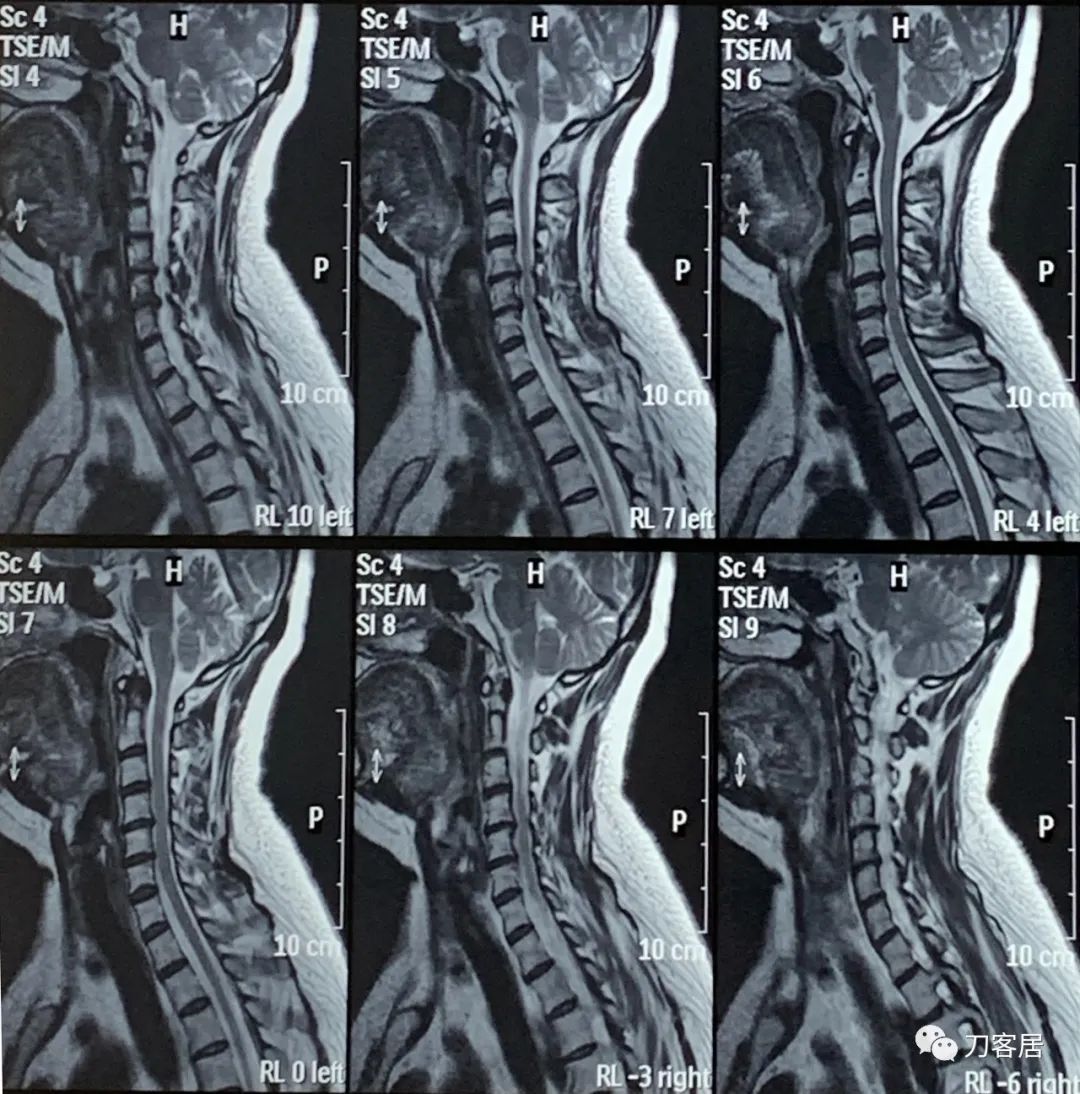

然后,2022年4月11日,患者又在当地另一家医院做了一次颈椎磁共振。

图27. 20220411平凉人民医院颈椎MRI01

图28. 20220411平凉人民医院颈椎MRI02

图29. 20220411平凉人民医院颈椎MRI03

图30. 20220411平凉人民医院颈椎MRI04

图31. 20220411平凉人民医院颈椎MRI05

图32. 20220411平凉人民颈椎MRI报告